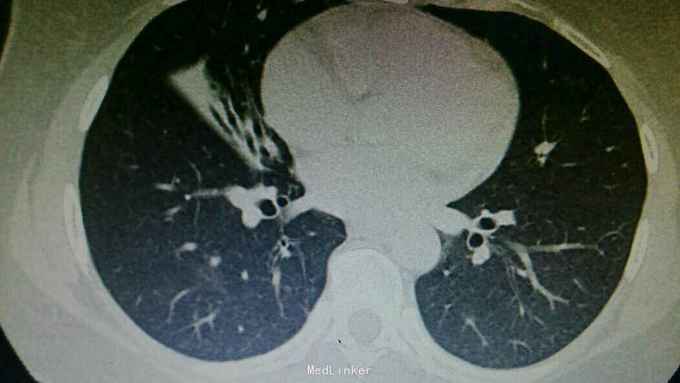

主诉:咳嗽8天,咯血6天。 病史:患者自诉8天前无明显诱因出现咳嗽,为刺激性干咳,未予以处理,6天前出现咯血,具体量不祥,为求诊治,入住我科。

查体:右下肺闻及湿性啰音,余无特殊。 辅查:胸部CT:右肺中上叶支扩并感染,双肺下叶磨玻璃影,考虑肺泡内积血可能。

诊断:支扩并咯血。 治疗:入院予以抗感染,止血,止咳化痰等治疗。